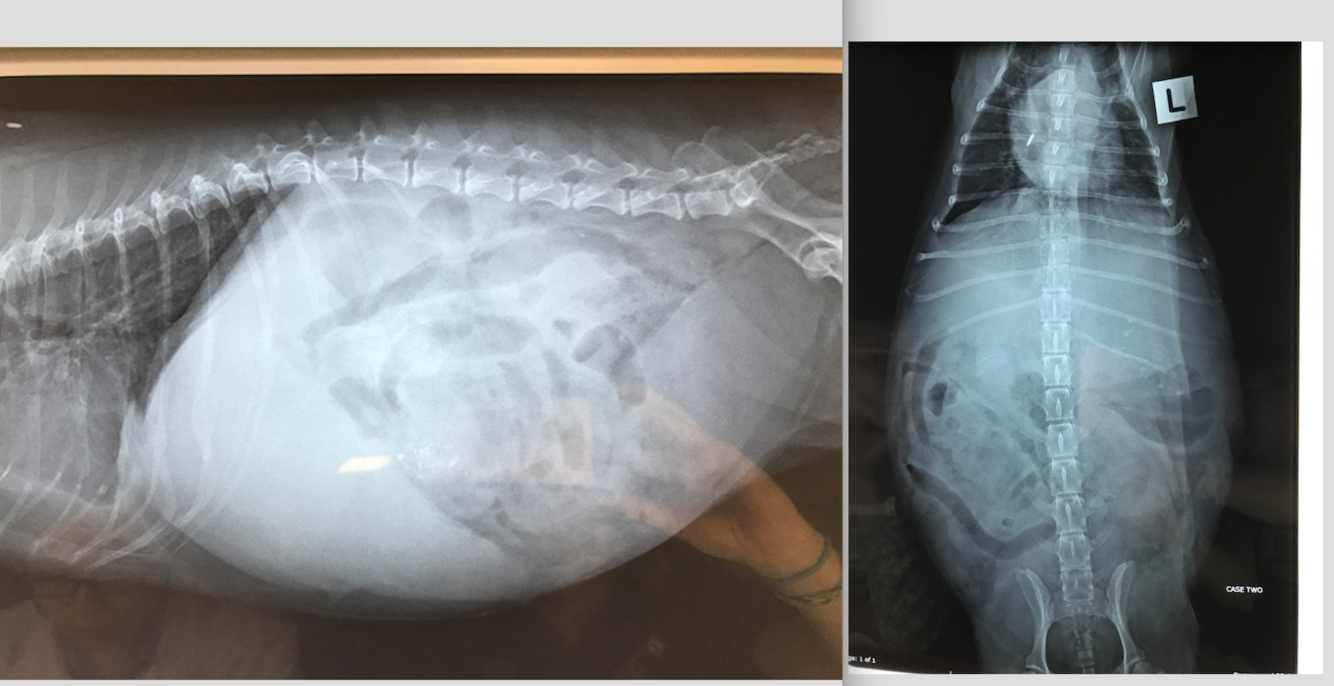

9 week old Male Labrador

Hx: Vomiting and anorexia for 2 days

HR 144 RR 36 Temp 39.7C NAD on abdo palpation

* Why decreased serosal detail?

* The gas within the GIT– which parts contain gas? Are the gas filled portions of the GIT over distended?

* The fluid filled portions– which parts contain fluid? Are they over distended?

* Which other organs can you ID? Are these within normal limits?

* What are your recommendations for further investigation and treatment of Baughie?